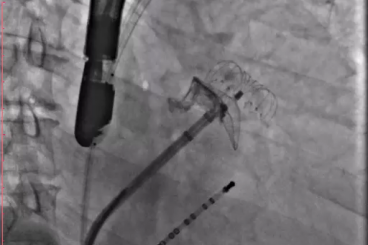

▲结束后取出脑保护装置,均未见血栓

其中首场公开演示的左心耳血栓封堵病例具有极高难度,患者术前TEE显示左心耳血栓形成伴机化,血栓位于心耳中段,近中端絮状物明显。封堵机会只有一次,选型和操作稍有失误,都会增加手术风险。因此手术采取全麻,并安装了抗栓塞脑动脉保护装置,以减少术中风险。通过TEE引导下测量左心耳大小以及确认左心耳血栓位置,李岳春教授凭借自身丰富经验最终决定使用LAmbre 2632型号,采用推送式植入法将左心耳血栓牢牢锁死于远端,并且封堵器一次成型,封堵效果极佳,结束后取出脑保护装置,均未见血栓,顺利完成了此台高难度的手术,获得了学员们的一致认可。